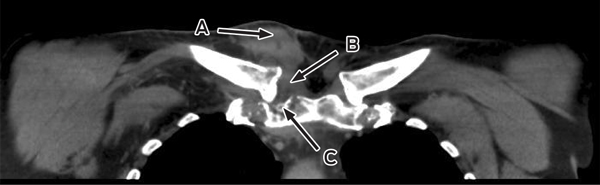

Further questioning found that the patient had a recent history of travel to South-East Asia and previous use of fluoroquinolone antibiotics. He was treated with intravenous cephazolin but his temperature continued to spike above 38°C. Magnetic resonance imaging (MRI) of his pelvis revealed a large prostatic abscess (Box 1), which was drained by transurethral resection. Tissue culture was consistent with the MDR E. coli previously isolated.

Despite ongoing cephazolin therapy, the patient developed increasing pain over the right sternoclavicular joint. Computed tomography imaging demonstrated changes consistent with a joint effusion, localised oedema, septic arthritis and osteomyelitis of the upper manubrium and medial right clavicle (Box 2). After initial conservative management without symptom resolution, surgical debridement was performed, and culture of the excised tissue grew MDR E. coli. The patient subsequently complained of lumbar back pain, and MRI of the lumbar spine showed changes consistent with an epidural abscess together with immediately adjacent discitis and osteomyelitis at the L4–5 vertebrae (Box 3). An orthopaedic consultation recommended conservative management, and the patient’s primary care was transferred to infectious diseases physicians. After 5 weeks of intravenous cephazolin therapy in hospital, he was discharged with a treatment regimen of intravenous ceftriaxone 2 g daily delivered by an elastomeric infusion device (Baxter) managed by the home-based acute care service.